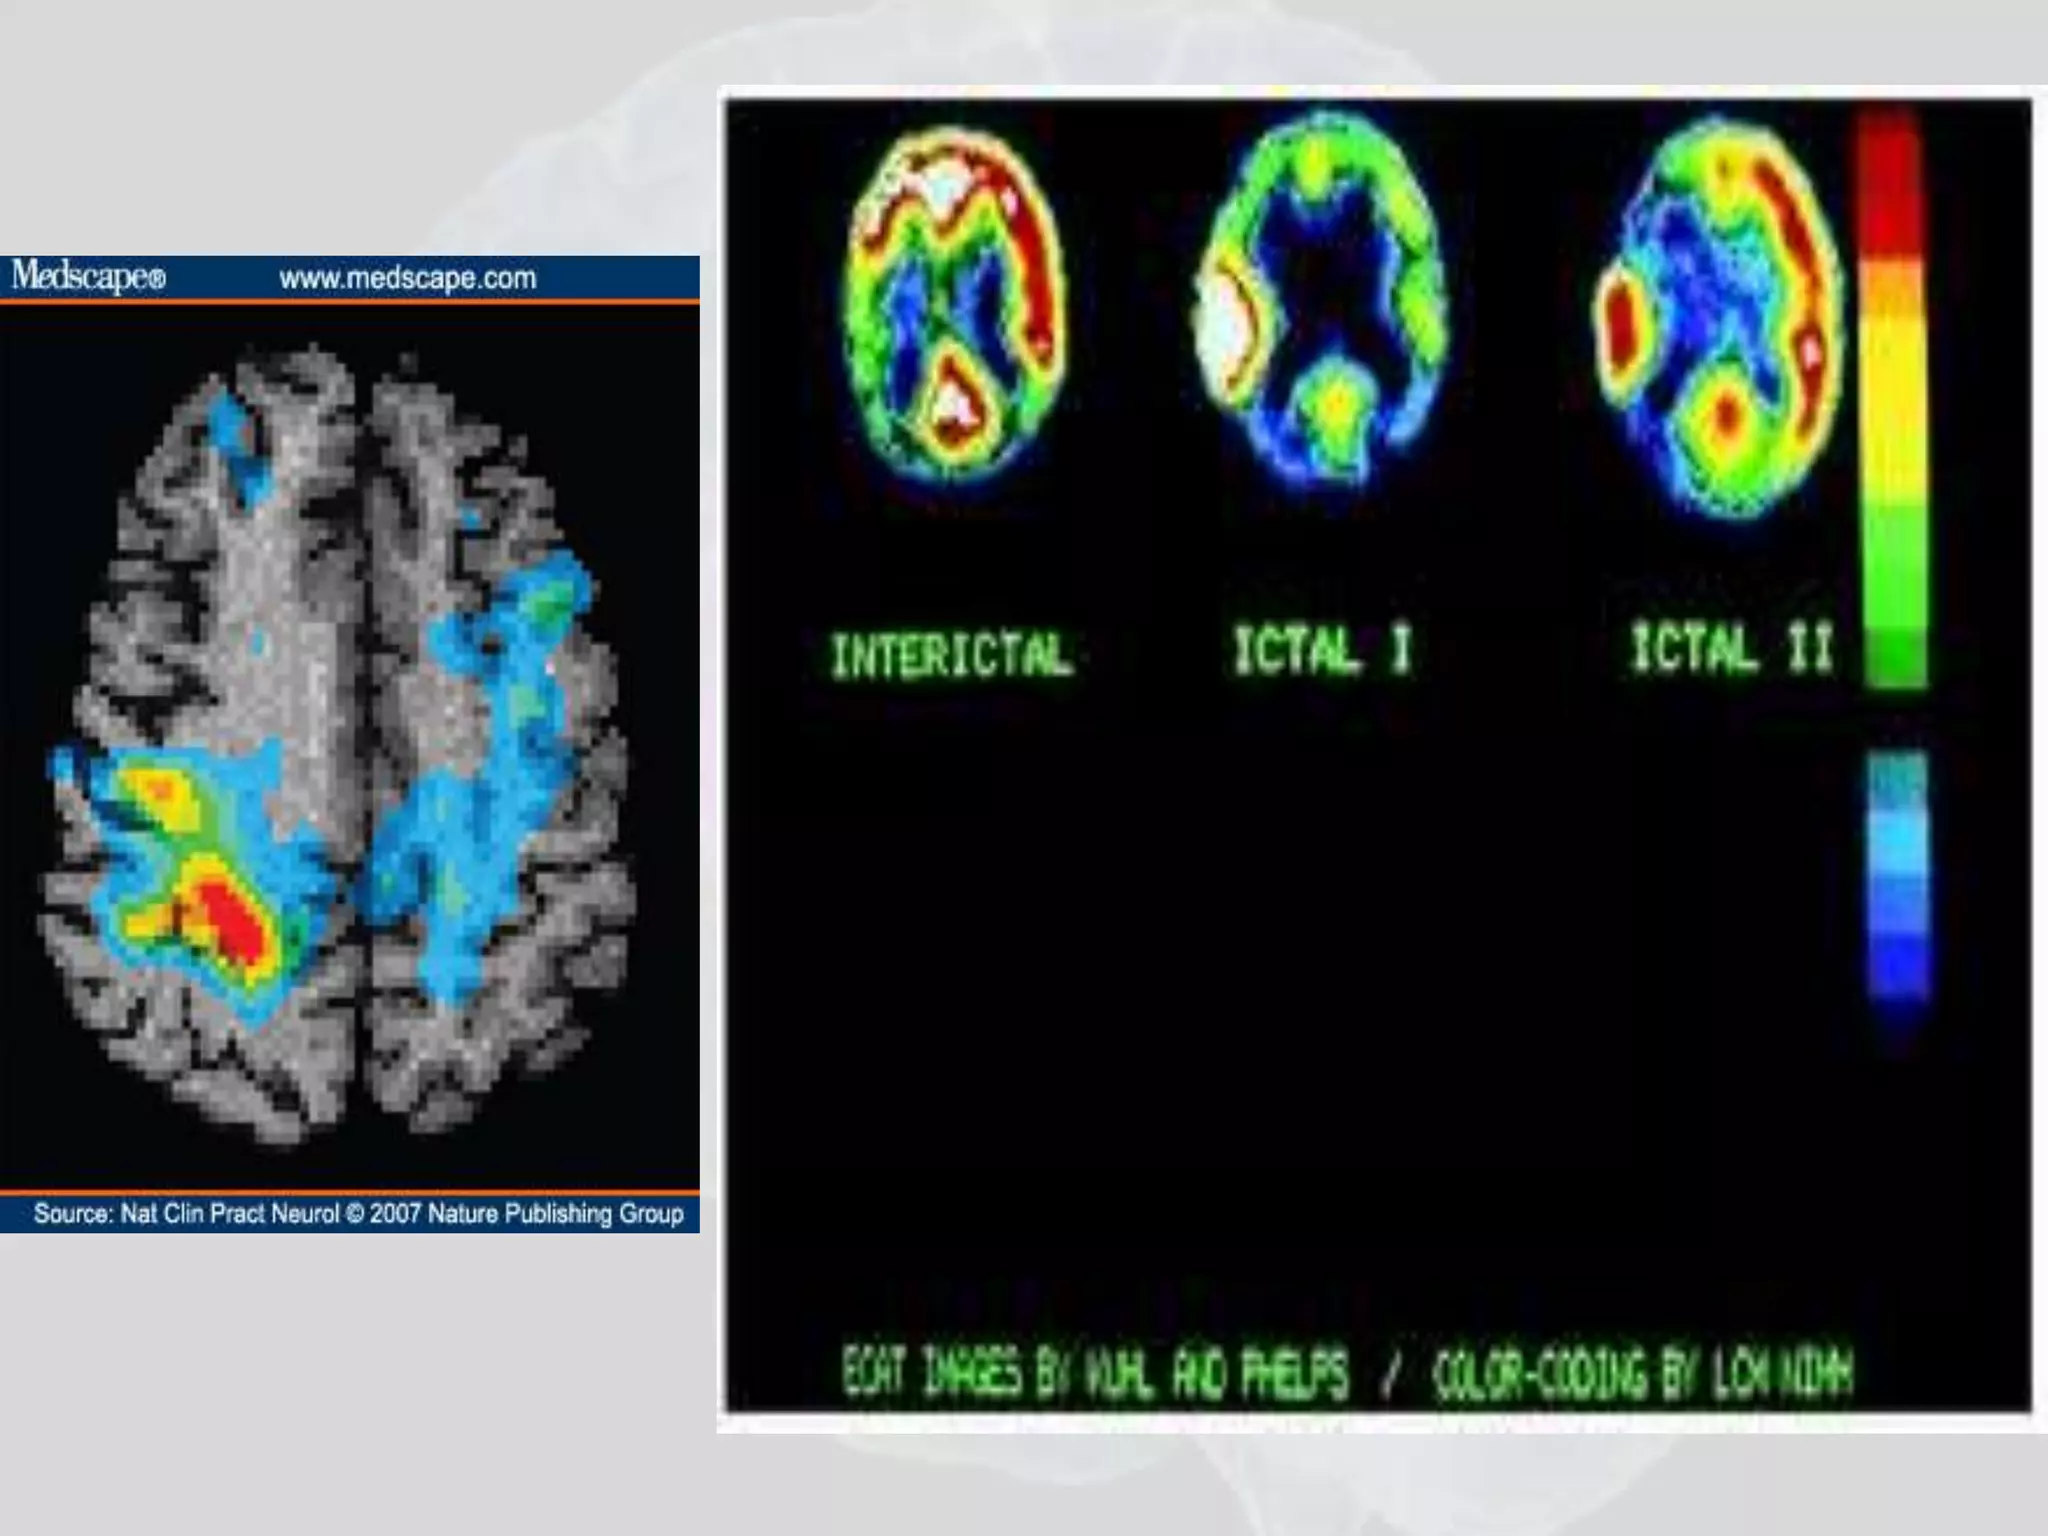

PET SCAN

• Positron emission tomography (PET) is a non-invasive

diagnostic imaging procedure that assesses the level of

metabolic activity and perfusion in various organ

systems of the human body.

• A positron camera (tomograph) is used to produce

cross-sectional tomographic images, which are

obtained from positron emitting radioactive tracer

substances (radiopharmaceuticals) such as 2-[F-18]

fluoro-d-glucose (FDG) that are administered

intravenously to the pt.

• Most common indication is for diagnosis and staging

for cancers.

PET- SCAN

• Positron emission tomography (PET) proving

usefulness in certain aspects of brain deseases

by showing differences in local brain

metabolism but is expensive and is only

available at special centres.

Pet scan indication

• Most common indication is for diagnosis and

staging for cancers.

• Refractory epilepsy

• Parkinsonism

• Dementia

• Neurodegenerative disoder

• Brain & spinal cord tumor

• Neuroendocrine tumors

Acadeny of medicine singapur

• Epilepsy

• Between seizures, a PET scan displays

decreased metabolism in the area of the

seizure and increased metabolism in the same

area during a seizure.

PET SCAN •Positron emission tomography (PET) is a non-invasive diagnostic imaging procedure that assesses the level of metabolic activity and perfusion in various organ systems of the human body. • A positron camera (tomograph) is used to produce cross-sectional tomographic images, which are obtained from positron emitting radioactive tracer substances (radiopharmaceuticals) such as 2-[F-18] fluoro-d-glucose (FDG) that are administered intravenously to the pt. • Most common indication is for diagnosis and staging for cancers.

PET- SCAN •Positron emission tomography (PET) proving usefulness in certain aspects of brain deseases by showing differences in local brain metabolism but is expensive and is only available at special centres.

Pet scan indication • Most common indication is for diagnosis and staging for cancers. • Refractory epilepsy • Parkinsonism • Dementia • Neurodegenerative disoder • Brain & spinal cord tumor • Neuroendocrine tumors Acadeny of medicine singapur

• Epilepsy •Between seizures, a PET scan displays decreased metabolism in the area of the seizure and increased metabolism in the same area during a seizure.